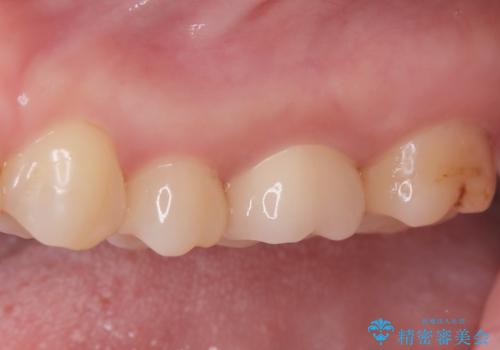

今回の治療では、虫歯の大きさや深さに応じて、異なるセラミック修復法を適用しました。

比較的軽度な虫歯には、セラミックインレー(詰め物)で対応し、健全な歯質を最大限に残しました。

進行した虫歯や歯の強度が低下している歯には、セラミッククラウン(被せ物)を選択し、歯全体を保護することで破折を防ぎました。

短期間での治療を可能にしつつ、天然歯と見分けがつかない審美性と、長期的に安定する機能性を兼ね備えたセラミック修復を実現しました。